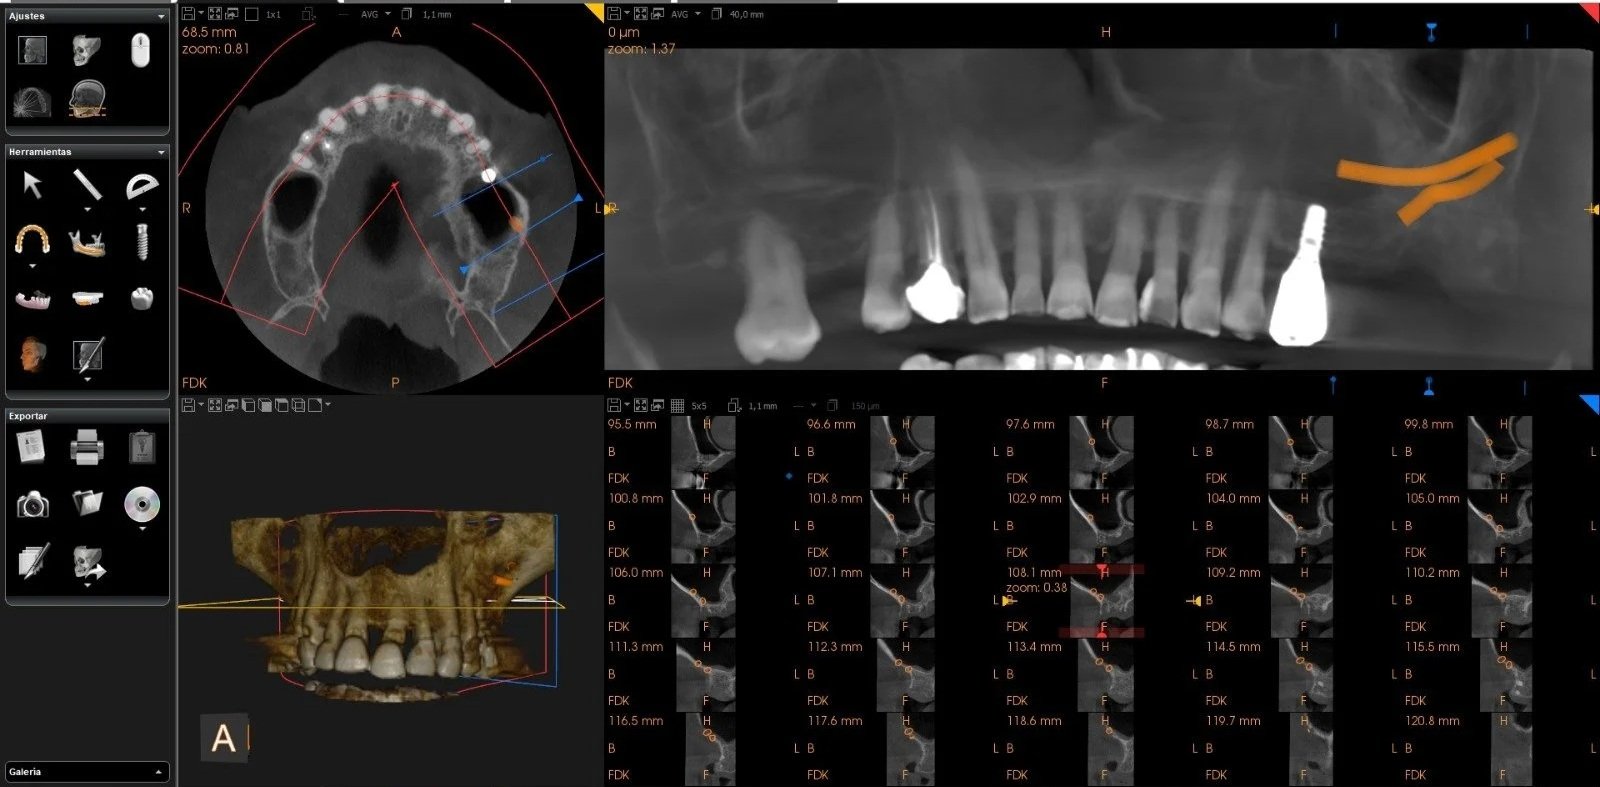

Tomografía